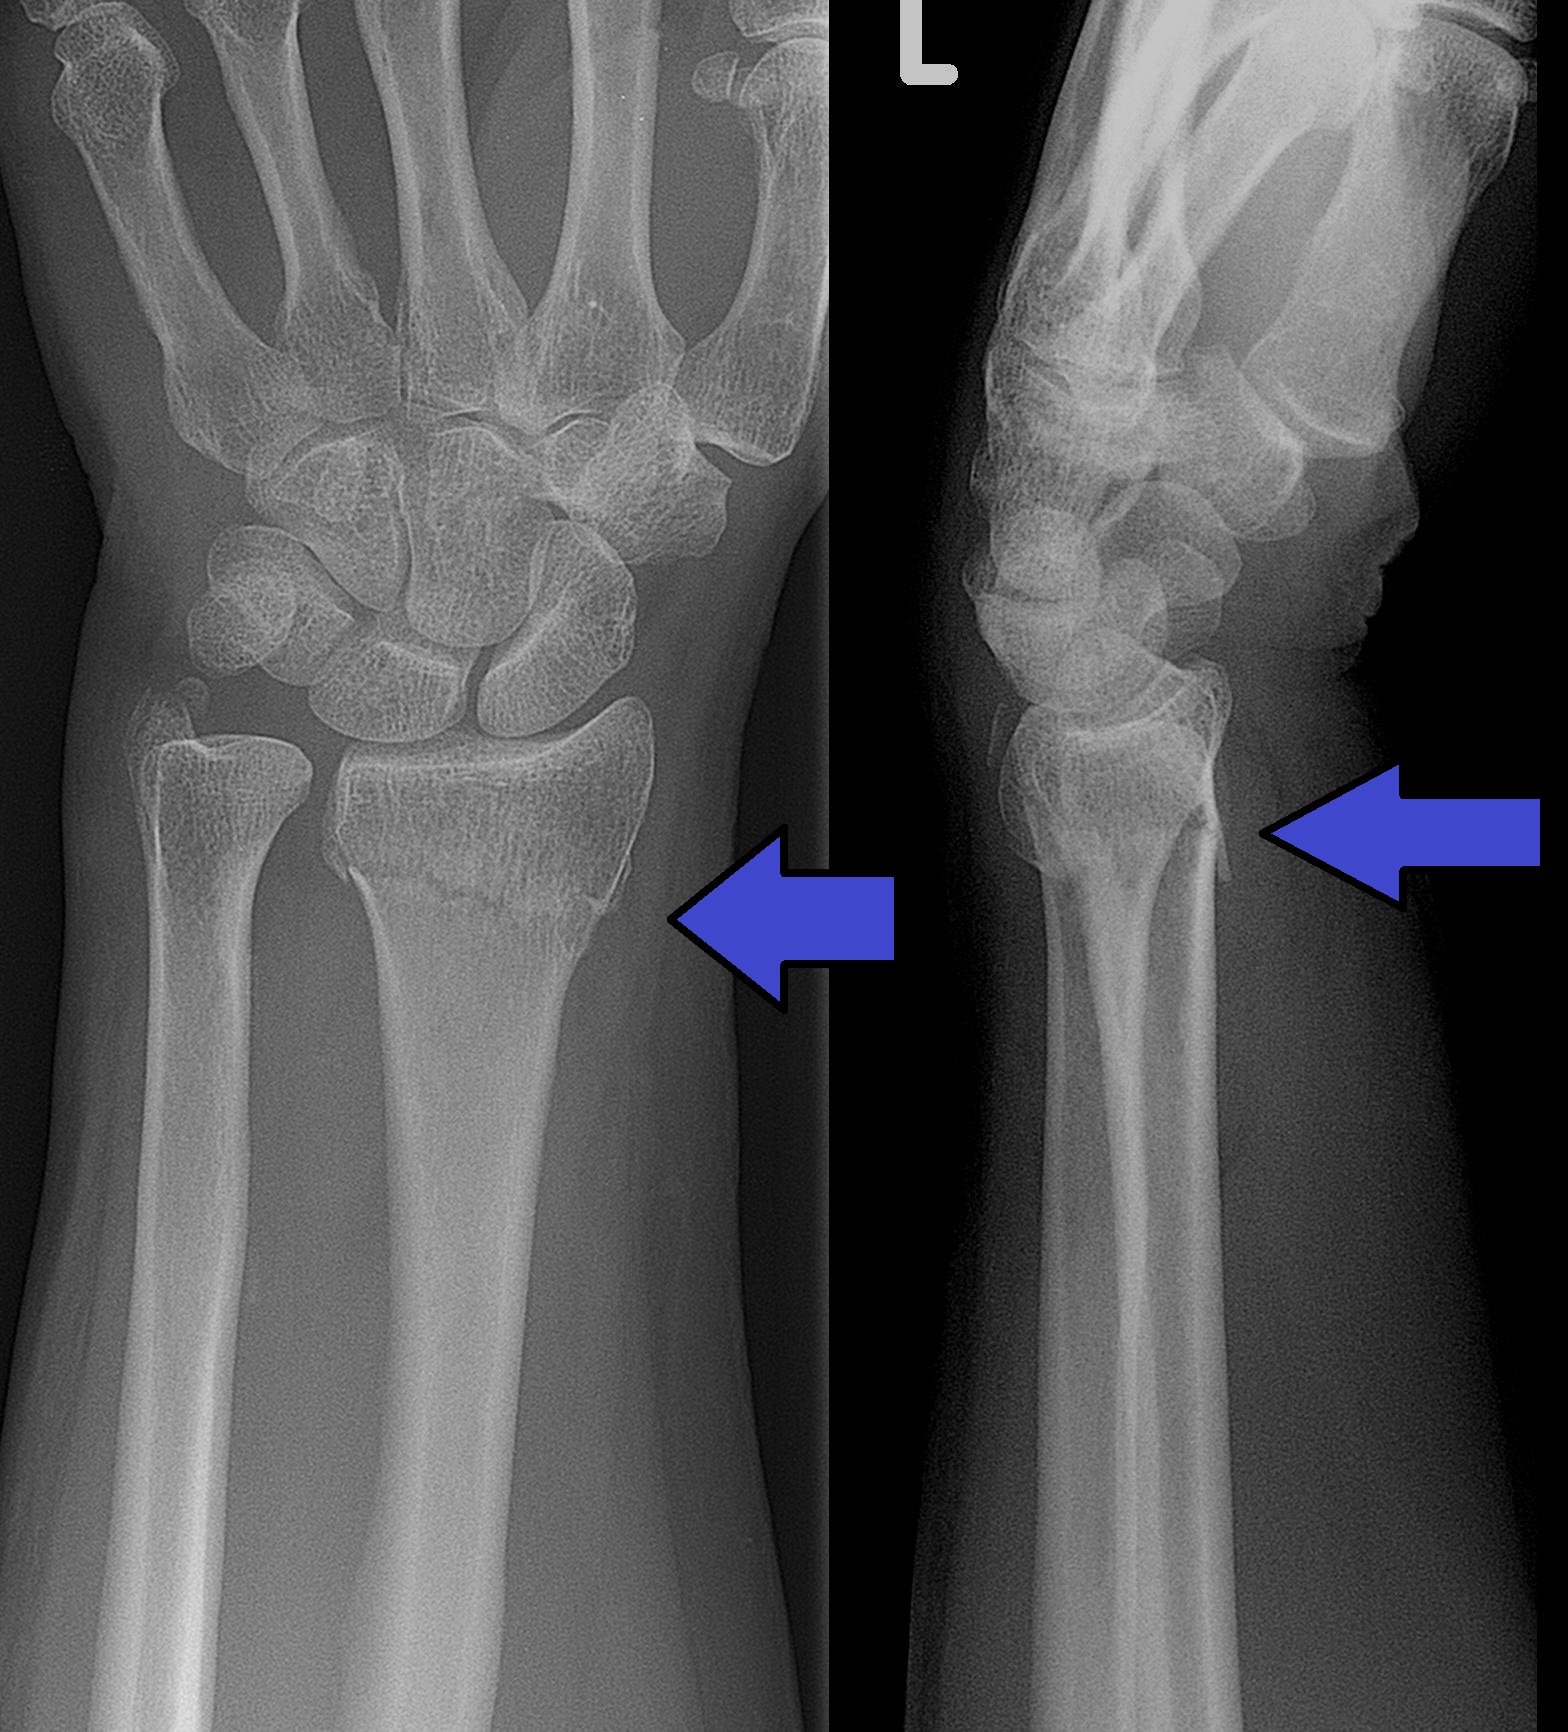

Wrist Fractures

Bone injuries due to falls or accidents.

A detailed assessment helps us understand the root cause of wrist or hand pain. During the evaluation, our orthopedic specialist examines joint movement, grip strength, swelling, tenderness, and other symptoms. When necessary, imaging tests such as X rays or scans may be recommended to confirm the diagnosis and guide the treatment plan.This thorough approach ensures accurate identification of the problem and supports effective treatment planning.

Diagnosis usually involves a physical examination along with imaging tests such as X-rays, MRI, or CT scans to identify fractures, ligament injuries, nerve compression, or joint problems.